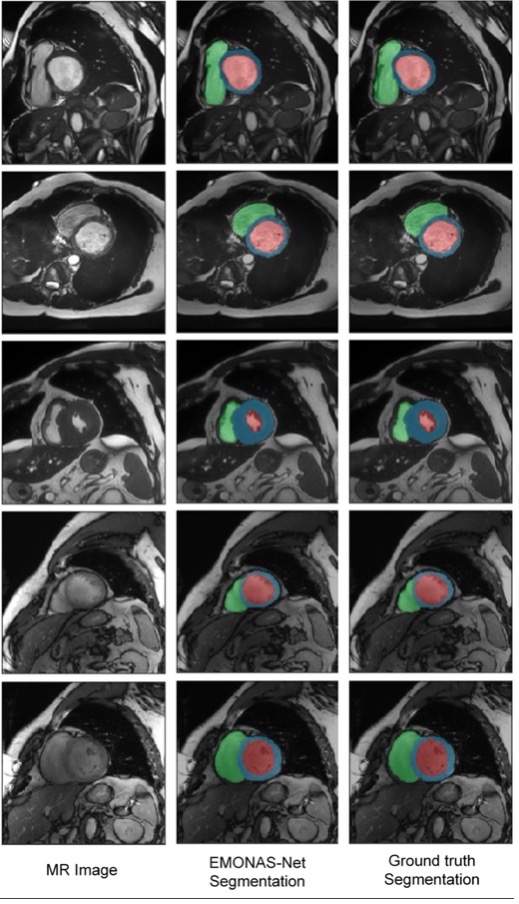

EMONAS-Net: A network that automatically segments medical images to facilitate diagnosis.

Publication title: EMONAS-Net: Efficient multiobjective neural architecture search using surrogate-assisted evolutionary algorithm for 3D medical image segmentation

Accurately segmenting medical images is a critical task to study anatomical structures, identify regions such as tumors and lesions, and assist in diagnosis. Nevertheless, manually segmenting images is a time-consuming process that requires expert knowledge. In this work, a framework that automatically designs neural networks that segment medical images is presented. The proposed neural networks produce accurate, consistent, and fast segmentations in prostate, cardiac, and brain MRIs.